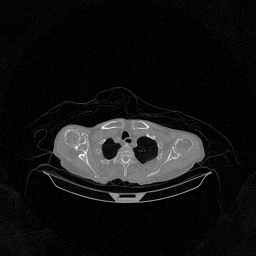

The results for simulated noisy data are shown in Fig. 2. The first and third rows display two representative slices from the test set, and the second and fourth rows present the corresponding error maps. The traditional WCE method suppresses cupping artifacts and recovers some missing anatomical structures but still shows noticeable deviations from the ground truth. Predictions from the four diffusion-based models demonstrate a markedly improved ability to restore anatomical structures. Among them, cDDPM fails to fully reconstruct the patient bed and retains residual noise in its outputs. This noise is attributable to an incomplete reverse denoising process rather than residual Poisson noise, as evidenced in our noise-free experiments (Fig. 5 in the Appendix). PatchDiffusion, diffusionGAN, and I2SB achieve similar visual quality, with I2SB producing the cleanest and most consistent reconstructions.

Quantitative results in Tab. V further confirm I2SB’s superiority over conventional deep learning methods such as FBPConvNet and Pix2pixGAN across RMSE, PSNR, and SSIM. Compared to other diffusion models—including cDDPM, PatchDiffusion, and cLDM—I2SB delivers higher image quality, while diffusionGAN achieves comparable quantitative performance. However, I2SB demonstrates a significant advantage in inference efficiency, as summarized in Tab. IV.

III-D Real Clinical Data Experiment

The experimental results on clinical head data are shown in Fig. 4. The reference images were reconstructed using the fast iterative shrinkage-thresholding algorithm (FISTA) with total variation regularization from non-truncated projection data. In the WCE reconstructions (Fig. 4(b)), severe truncation prevents accurate recovery of anatomical structures outside the FOV. Despite being trained solely on simulated data with a domain gap, all deep learning models can restore a substantial portion of the missing anatomy. Among them, the diffusion-based methods recover soft-tissue boundaries more faithfully than the conventional deep learning approach FBPConvNet, highlighting their stronger image generation capability. However, cDDPM reconstructions exhibit more noticeable noise than those from other methods, consistent with the simulated data results. The patchDiffusion model introduces artifacts within the FOV, likely due to its patch-wise processing strategy. While I2SB shares the same limitations as other diffusion models in perfectly restoring soft-tissue detail, it produces fewer residual noise patterns and fewer artifacts within the FOV boundaries. Overall, Fig. 4 demonstrates the strong efficacy of I2SB in reconstructing real CBCT data.